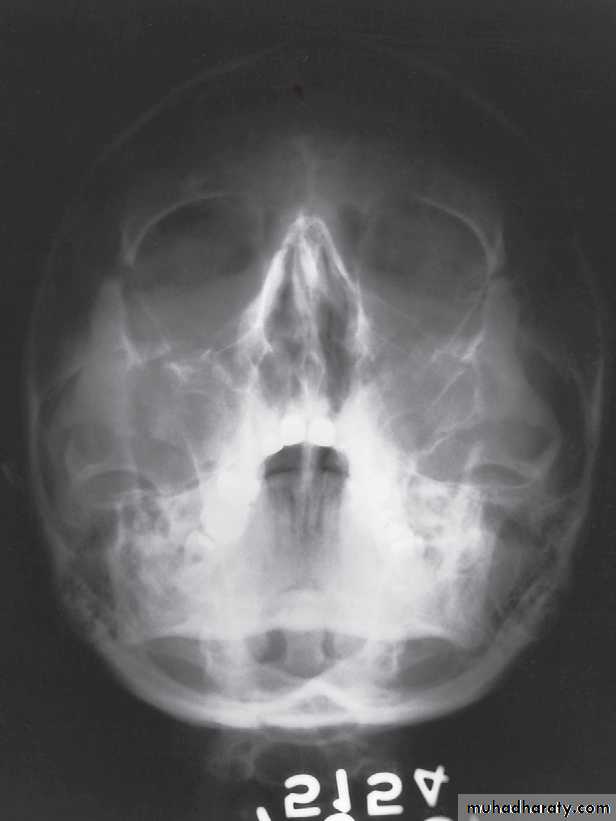

Waters’ View

Caldwell’s View